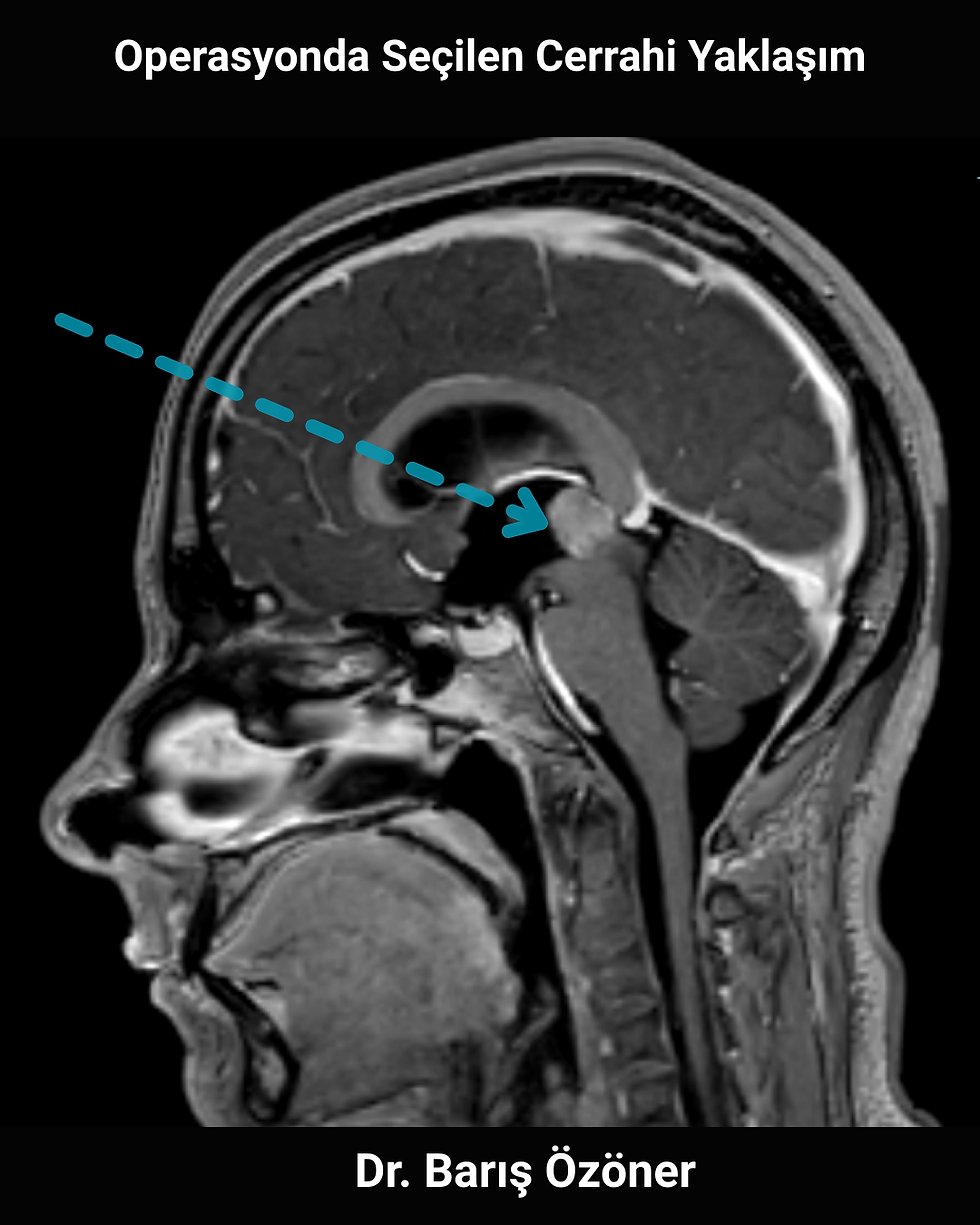

İkinci görselde tümörün önde yerleşimi ve komşu yapılarla ilişkisi nedeniyle ön taraftan (anterior) bir cerrahi yaklaşımın planlandığı MR kesiti görülmektedir.